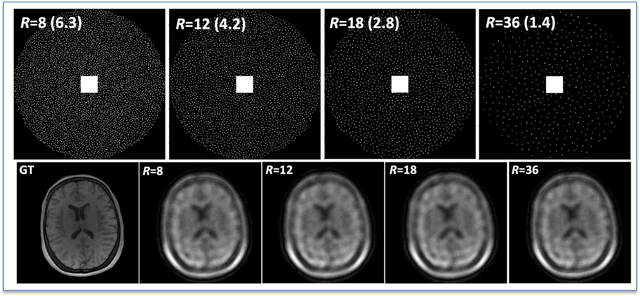

Abstract:The purpose of this work is to implement physics-based regularization as a stopping condition in tuning an untrained deep neural network for reconstructing MR images from accelerated data. The ConvDecoder neural network was trained with a physics-based regularization term incorporating the spoiled gradient echo equation that describes variable-flip angle (VFA) data. Fully-sampled VFA k-space data were retrospectively accelerated by factors of R={8,12,18,36} and reconstructed with ConvDecoder (CD), ConvDecoder with the proposed regularization (CD+r), locally low-rank (LR) reconstruction, and compressed sensing with L1-wavelet regularization (L1). Final images from CD+r training were evaluated at the \emph{argmin} of the regularization loss; whereas the CD, LR, and L1 reconstructions were chosen optimally based on ground truth data. The performance measures used were the normalized root-mean square error, the concordance correlation coefficient (CCC), and the structural similarity index (SSIM). The CD+r reconstructions, chosen using the stopping condition, yielded SSIMs that were similar to the CD (p=0.47) and LR SSIMs (p=0.95) across R and that were significantly higher than the L1 SSIMs (p=0.04). The CCC values for the CD+r T1 maps across all R and subjects were greater than those corresponding to the L1 (p=0.15) and LR (p=0.13) T1 maps, respectively. For R > 12 (<4.2 minutes scan time), L1 and LR T1 maps exhibit a loss of spatially refined details compared to CD+r. We conclude that the use of an untrained neural network together with a physics-based regularization loss shows promise as a measure for determining the optimal stopping point in training without relying on fully-sampled ground truth data.